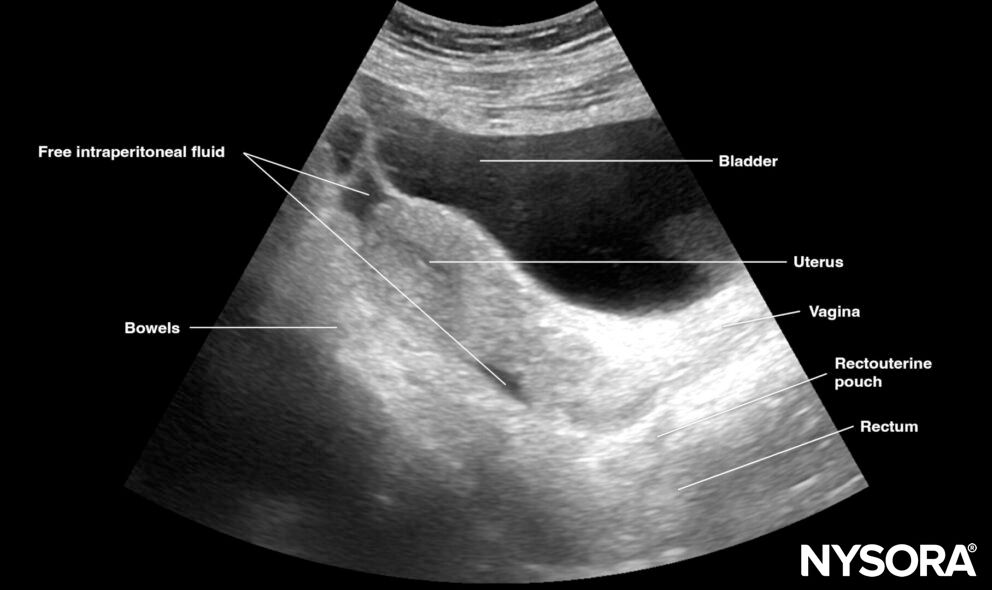

Free intraperitoneal fluid:

Pelvic free fluid collects behind the bladder or the area lateral to the bladder (rectovesical pouch in men and the rectouterine pouch or pouch of Douglas in women).

Sagittal section through the pelvis with free fluid in the rectovesical pouch in men and the rectouterine pouch (pouch of Douglas) in women.

Sonoanatomy of interest in females:

Longitudinal view of the female pelvis with free fluid in the rectouterine pouch.